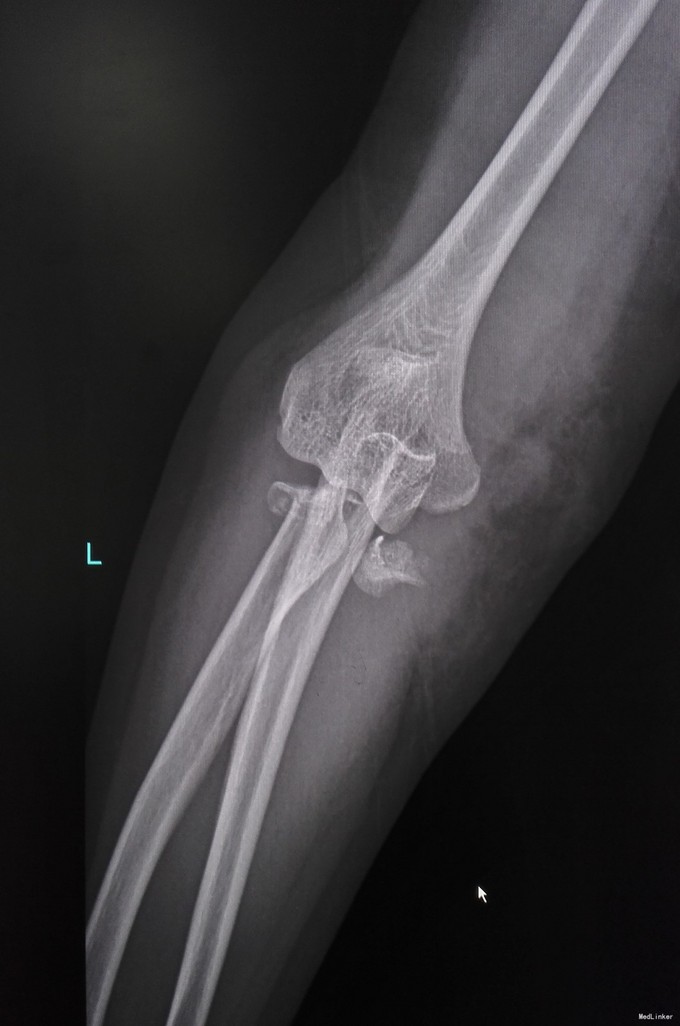

女性,67岁,车祸致右肘肿痛畸形1天入院

查体见右肘肿胀畸形严重,予以临时复位石膏固定,输液抬高消肿。

诊断为肘关节恐怖三联征(肘关节后脱位伴桡骨头和尺骨冠状突骨折),消肿后予以切开复位Wright桡骨小头假体置换,外侧副韧带修补,冠状突骨块小,未行固定。